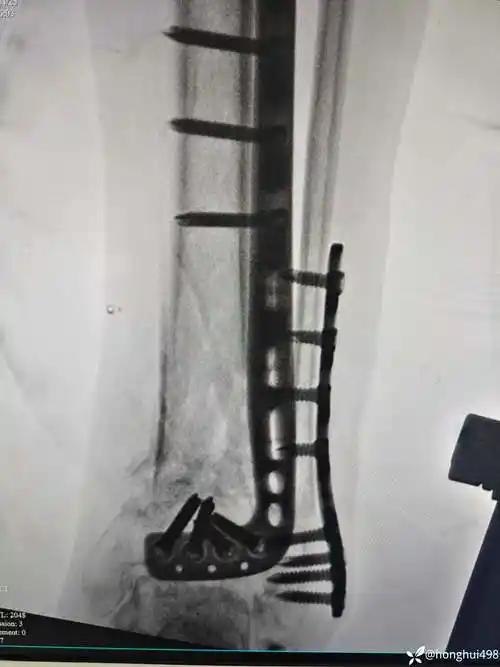

第一例胫骨远端前外侧"l"型钢板mippo内固定 [病例帖]

为什么侧面看手术后本来就是没有接好,没对准就装了钢板,有看得懂的吗